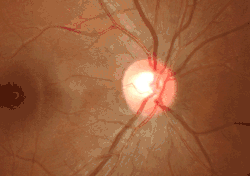

Almost all eye structures can be examined with appropriate optical equipment and lenses. Using a modern direct ophthalmoscope gives a view of the optic disc using the principle of reversibility of light. A slit lamp biomicroscopic examination along with an appropriate aspheric focusing lens (+66D, +78D or +90D) is required for a detailed stereoscopic view of the optic disc and structures inside the eye.

A biomicroscopic exam can indicate the health of the optic nerve. In particular, the eye care physician notes the colour, cupping size (as a cup-to-disc ratio), sharpness of edge, swelling, hemorrhages, notching in the optic disc and any other unusual anomalies. It is useful for finding evidence corroborating the diagnosis of glaucoma and other optic neuropathies, optic neuritis, anterior ischemic optic neuropathy or papilledema (i.e. optic disc swelling produced by raised intracranial pressure), and optic disc drusen.